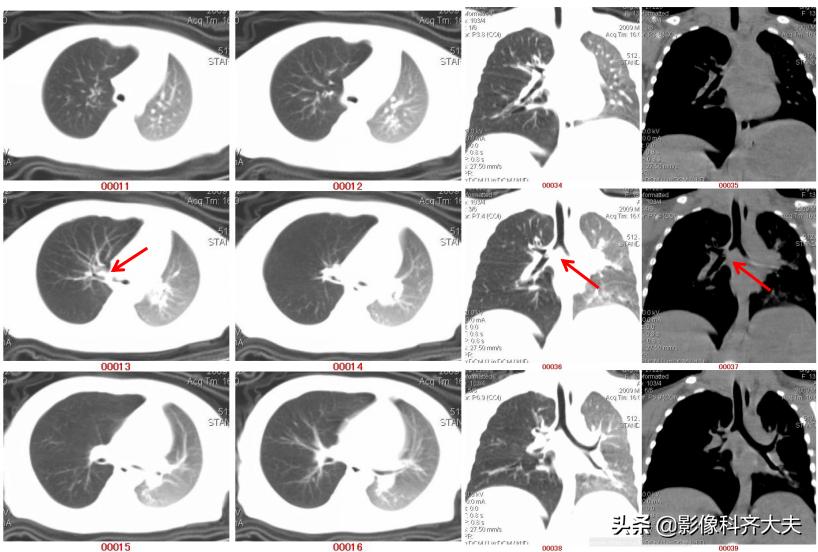

病例1、病史:患儿,女,一岁半,咳喘两周,病前有“开心果”吸入史。

图为轴位及冠状位重建图显示异物:红色箭头为异物的位置,冠状位显示尤为清晰。

病例3、病史:患儿,两岁半。咳嗽近一个月,外院按支气管炎治疗半个月无好转。询问家属是否有吃东西呛咳病史,家属回忆一个月前还在好像吃过花生,瓜子,但不能完全确定。

图像显示在气管分叉的位置有一“瓜子”形异物的存在,尤其是冠状位显示更明显。

病例4、病史:患者男、13岁,误食“钉子

轴位图

冠状位图

通过以上病例可见:CT的MPR冠状位,可直接发现异物的位置,形状和大小,以及邻近组织区域变化。